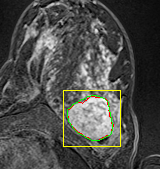

We tested the algorithm by varying the number of markers between and . Fig 2 describes the segmentation results obtained using different numbers of markers. This plot indicates that markers were found to be optimal using this segmentation approach, yielding satisfactory results.

where refers to the ROIs segmented by our algorithm and is tumor area as determined by manual segmentation. Table 1 summarizes the segmentation accuracy achieved using the proposed method for all 106 cases. The average dice coefficient was found to be 0.780.17 and average Jaccard index was 0.670.21. Fig 3 demonstrate four sample segmentation outputs which are overlaid on manual segmentations provided by two radiologists. It can be seen, that the proposed method could accurately segment the lesions with some marginal errors for medium to large tumors. However, for cases comprising disjoint lesions, the method failed to segment all small lesions and in some cases incorrectly labeled healthy tissue as lesions. This is because in some cases there is a high degree of overlap in the intensity distributions of healthy breast tissue and lesions, and the ROI drawn by the radiologist is very large in the case of disjoint lesions, in order to cover the entire area over which multiple lesions are distributed.